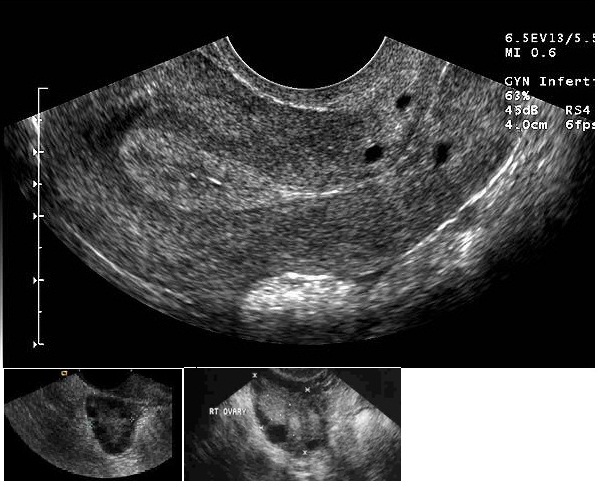

dc.description.abstractBeSt programmi toetusel valminud õpiobjekt "Korduv raseduse katkemine" on koostatud eesmärgiga anda sünnitusabi ja günekoloogia eriala spetsialistele, doktorantidele ja residentidele kaasajastatud ülevaade igapäevases kliinilises töös suhteliselt sageli esinevast probleemist. Õppematerjal koosneb nelja haigusjuhu analüüsist ja teoreetilisest osast, kus käsitletakse korduva raseduse riskitegureid, põhjusi ja ravi võimalusi. Õppematerjal sisaldab mitmeid testivormis küsimusi, mille abil saab hinnata oma teadmisi õppeprotsessi vältel. Kasutatud materjalid ja täiendavad infoallikad on toodud materjali lõpus teemade kaupa. Õppematerjali läbitöötamiseks kulub orienteeruvalt 10-12 tundi.et